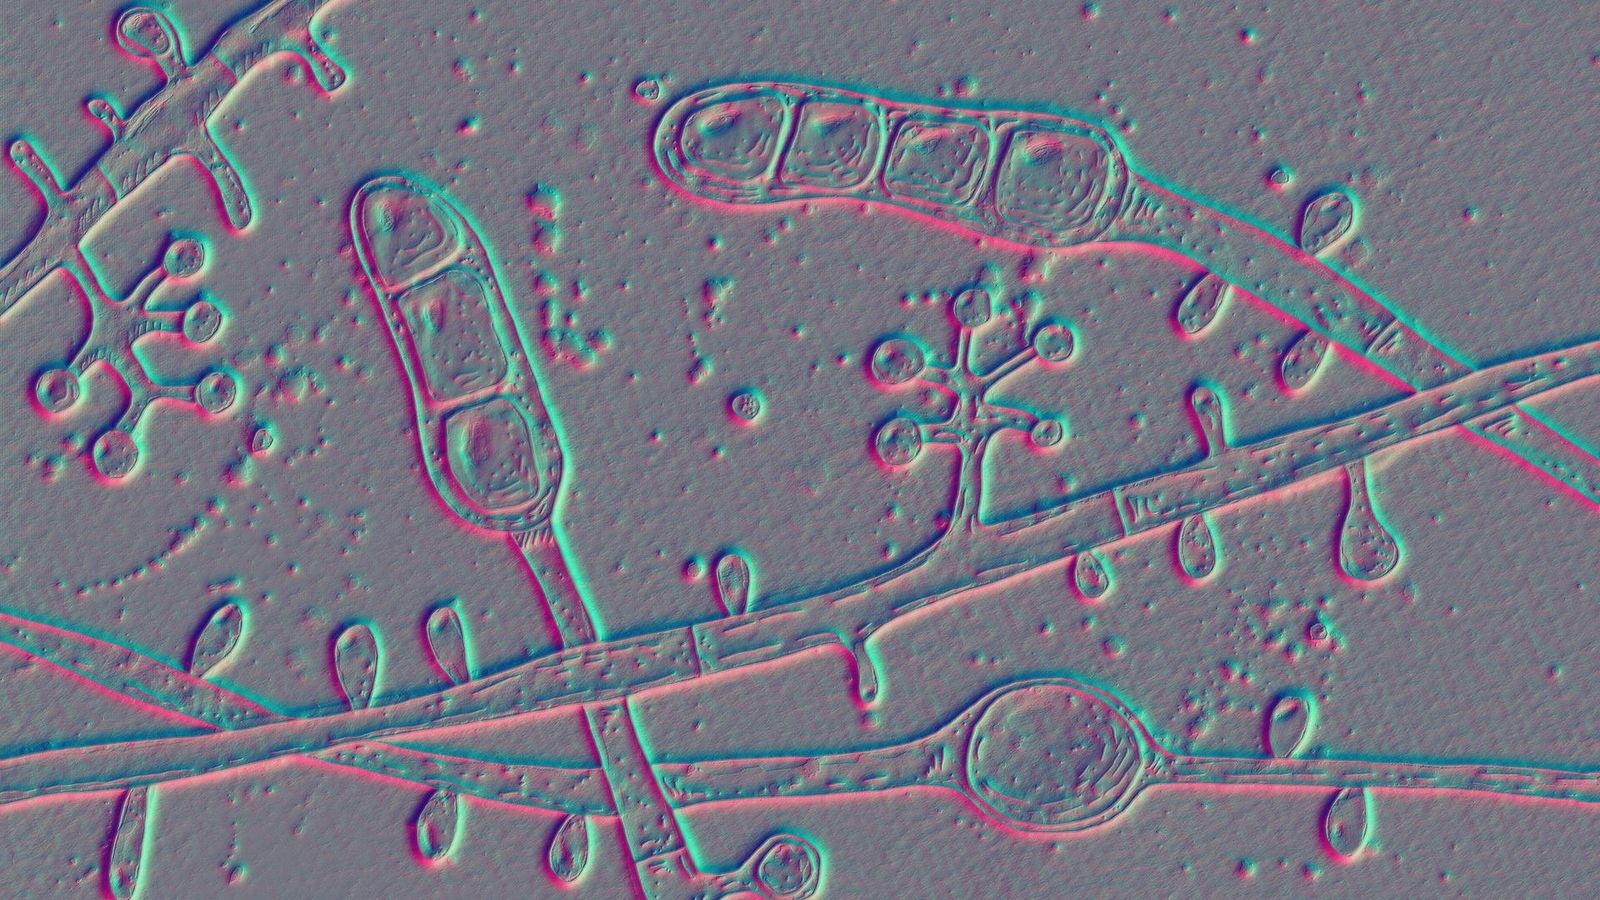

„Europaweite Epidemie“ von Trichophyton tonsurans: Was Sie zu dem aktuell grassierenden Hautpilz wissen müssen

Die Kopfhaut juckt und fühlt sich gereizt an, auf der Hautoberfläche bilden sich Schuppen und rote Flecken. Ein hochansteckender Fadenpilz verbreitet sich aktuell unter jungen Männern in Deutschland und...weiterlesen »

Düsseldorf · Die Kopfhaut juckt und fühlt sich gereizt an, auf der Hautoberfläche bilden sich Schuppen und rote Flecken. Ein hochansteckender Fadenpilz verbreitet sich aktuell unter jungen Männern in Deutschland...weiterlesen »